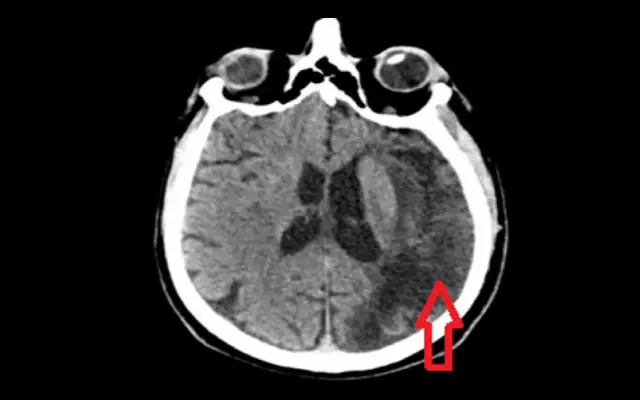

Udar czy wylew? Rozwiej wątpliwości! Poznaj różnice, objawy (U.D.A.R.), pierwszą pomoc i profilaktykę. Sprawdź, jak ratować życie!

Udar a wylew czy to to samo? Poznaj kluczowe różnice między udarem niedokrwiennym a krwotocznym. Dowiedz się, jak rozpoznać objawy (FAST) i dlaczego szybka reakcja ratuje życie. Przeczytaj!

Udar mózgu: poznaj jego przyczyny, typy i czynniki ryzyka. Dowiedz się, jak styl życia wpływa na zdrowie mózgu i jak skutecznie zapobiegać.